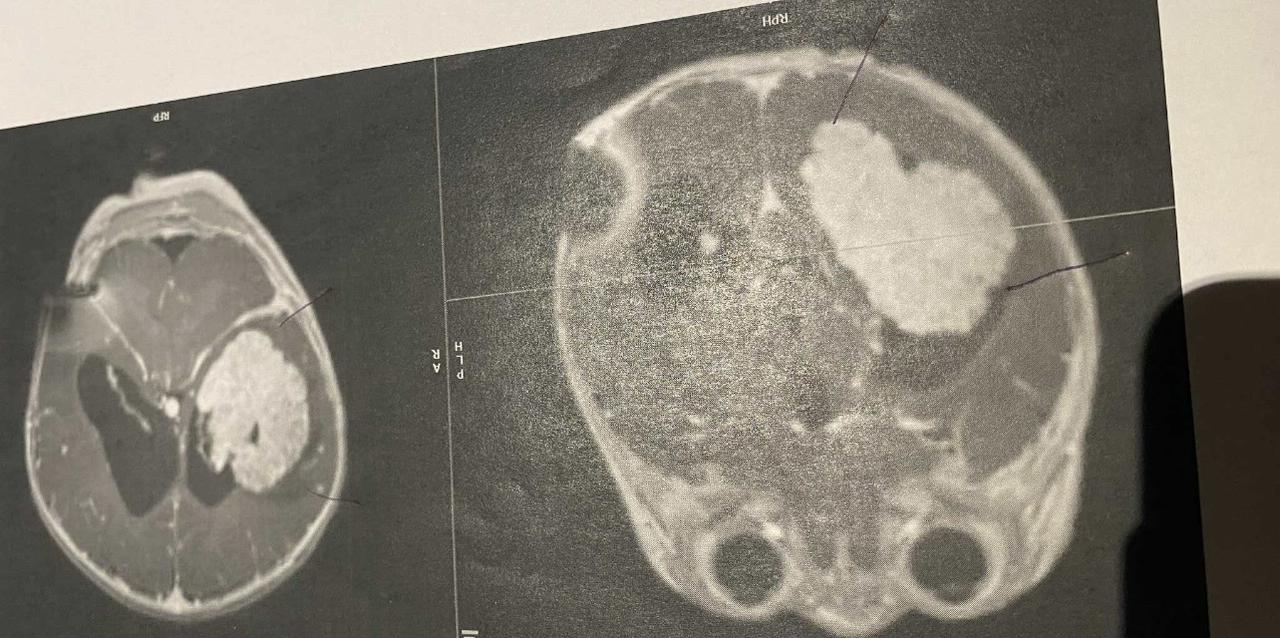

This handsome brave boy is 6 months old now and has successfully recovered from his big 9 hour surgery, which was first to stop the blood flow feeding the tumour followed by the surgery to remove the full tumour successfully. Unfortunately after the shunt was put in and a round of chemo was given to Baby Declan it showed the tumour had grown quite quickly so the urgency to remove the tumour came around quicker than we expected.

The very rare tumour Declan has was an Atypical choroid plexus papilloma we are still waiting on more tests to confirm and discuss the next steps.

Declan had his MRI post Chemo down in Wellington on the 9th December and unfortunately the chemo has not shrunk the tumour at all in fact it has grown we are heart broken 💔 Declan and his Dad have flown back to starship today and I will be driving up tomorrow (Sunday) as they are proceeding with the surgery Monday the 15th where they are hoping to remove the tumour safely but do a procedure before hand to stop the blood flow feeding the tumour. There are so many risks that we have been informed about re the surgery and we are really hoping for a positive outcome so please keep Baby Declan in your thoughts and Thank you to each and every one of you who have donated to help through this unfair time 🥹

Declan had 1 of his first surgeries and that was putting a shunt in so they can drain the excess fluid from his brain to his abdomen as removing the tumor isnt the best thing to do atm as he is still so tiny and would be life threating!

While the oncologist, surgical nurse and specialist came together they said the are concerned about a few bits the lit up in Declan's MRI, they suspect cancer.